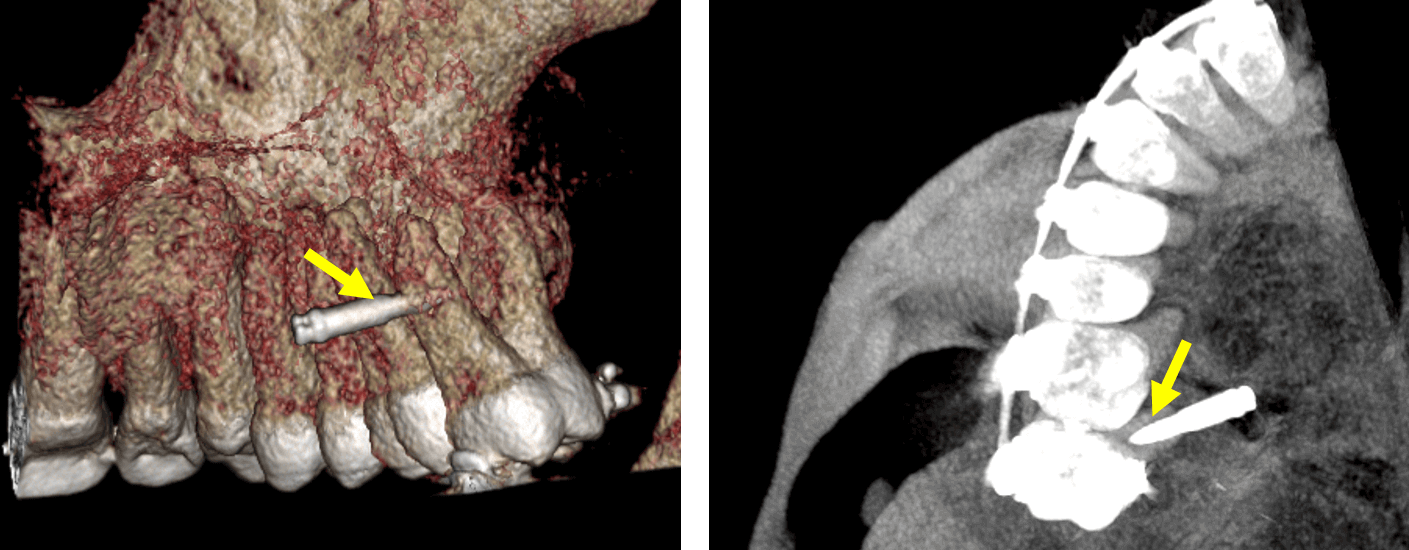

Fig.4

En cortes sagitales (Fig.4) se observa el dispositivo de fijación quirúrgica (flechas azules) comprometiendo el conducto radicular de la raíz palatina, donde también se observan los trazos de fractura (flechas rojas) en sentido superior e inferior en relación con la perforación del material hiperdenso.

Fig.5

En la representación tridimensional (Fig.5) se evidencia la perforación del dispositivo de fijación quirúrgica en la raíz palatina del órgano dentario 17.